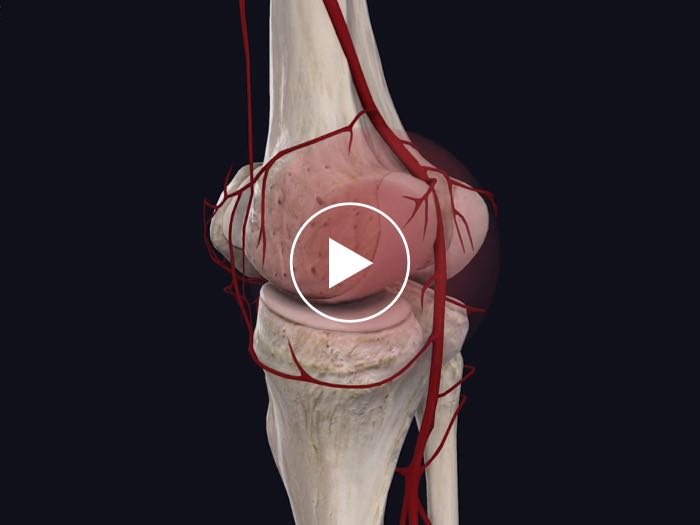

Arterial Supply

See the arteries that supply any muscle, and trace them back to the heart